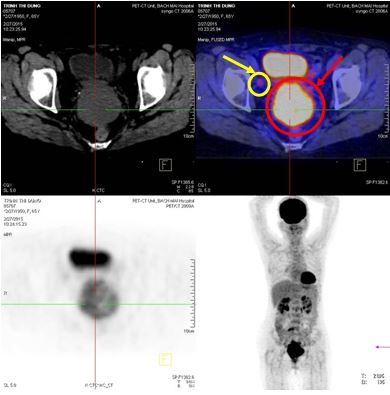

Chụp cộng hưởng từ tiểu khung cho thấy tử cung tư thế trung gian, kích thước bình thường, thành điều, nội mạc dày 5 mm, buồng tử cung không có dịch, không thấy khối khu trú. Vị trí thành trước buồng tử cung nghi ngờ có khối nhỏ kích thước 10x15mm ngấm thuốc mạnh sau tiêm. Vị trí cạnh bó mạch chậu 2 bên có vài hạch, hạch lớn nhất kích thước 18x23mm, trung tâm hạch hoại tử dạng dịch.

Hình 2. Hình ảnh cộng hưởng từ tiểu khung sau điều trị (khối u cổ tử cung thu nhỏ kích thước (mũi tên đỏ), hạch (mũi tên vàng)